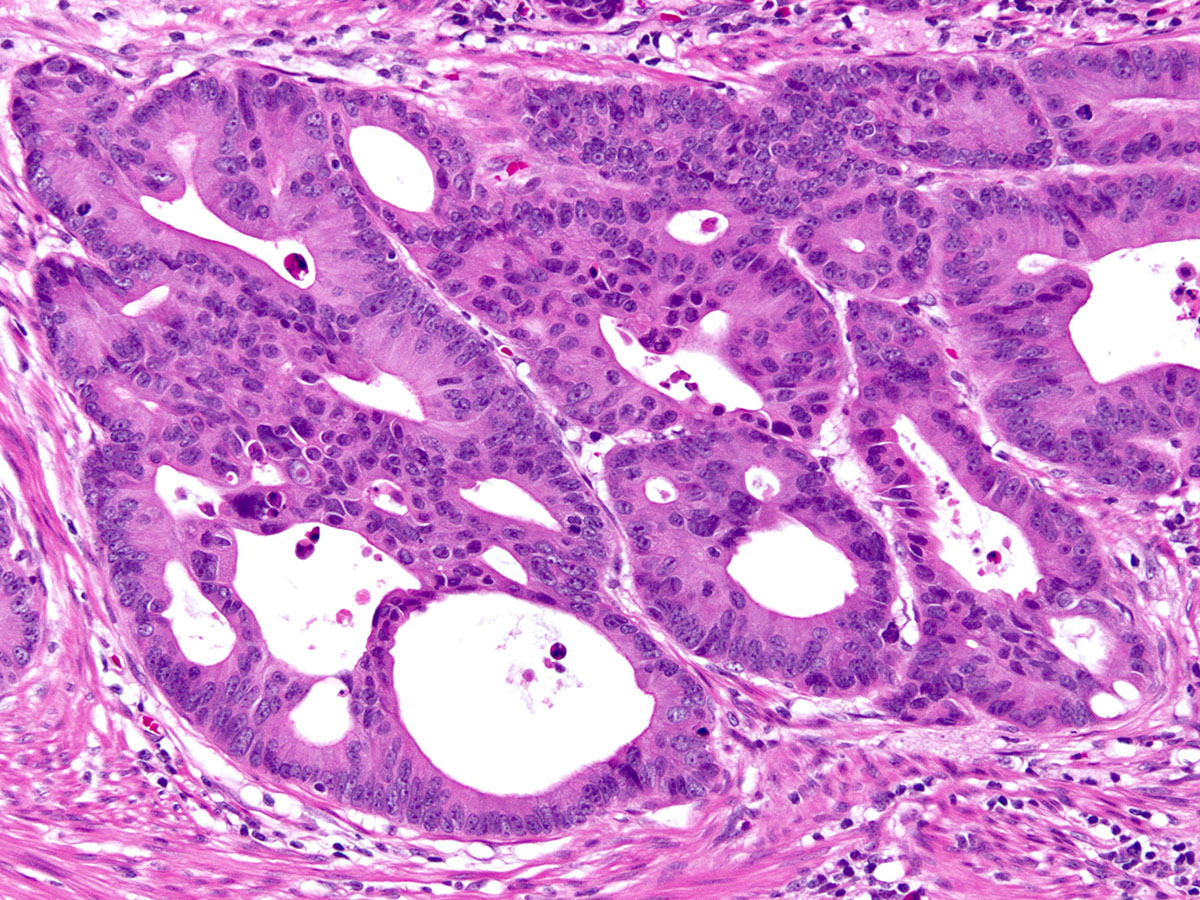

Cleveland Clinic Laboratories Industry Workshop with Jesse McKenney at ASCP 2017